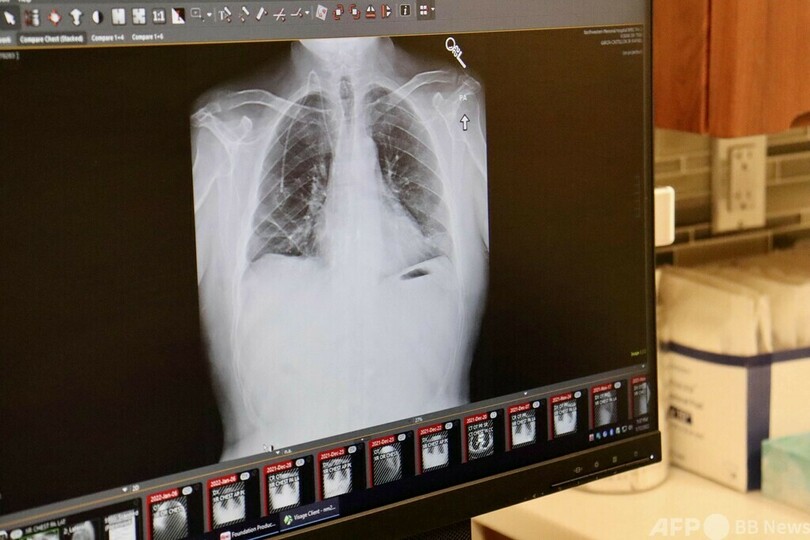

末期がん患者に両肺移植 米病院が成功

【3月25日 AFP】米シカゴの病院ノースウエスタン・メディシン(Northwestern Medicine)は25日、末期の肺がん患者への両肺移植が成功したと発表した。他の患者に希望を与える成果となる。